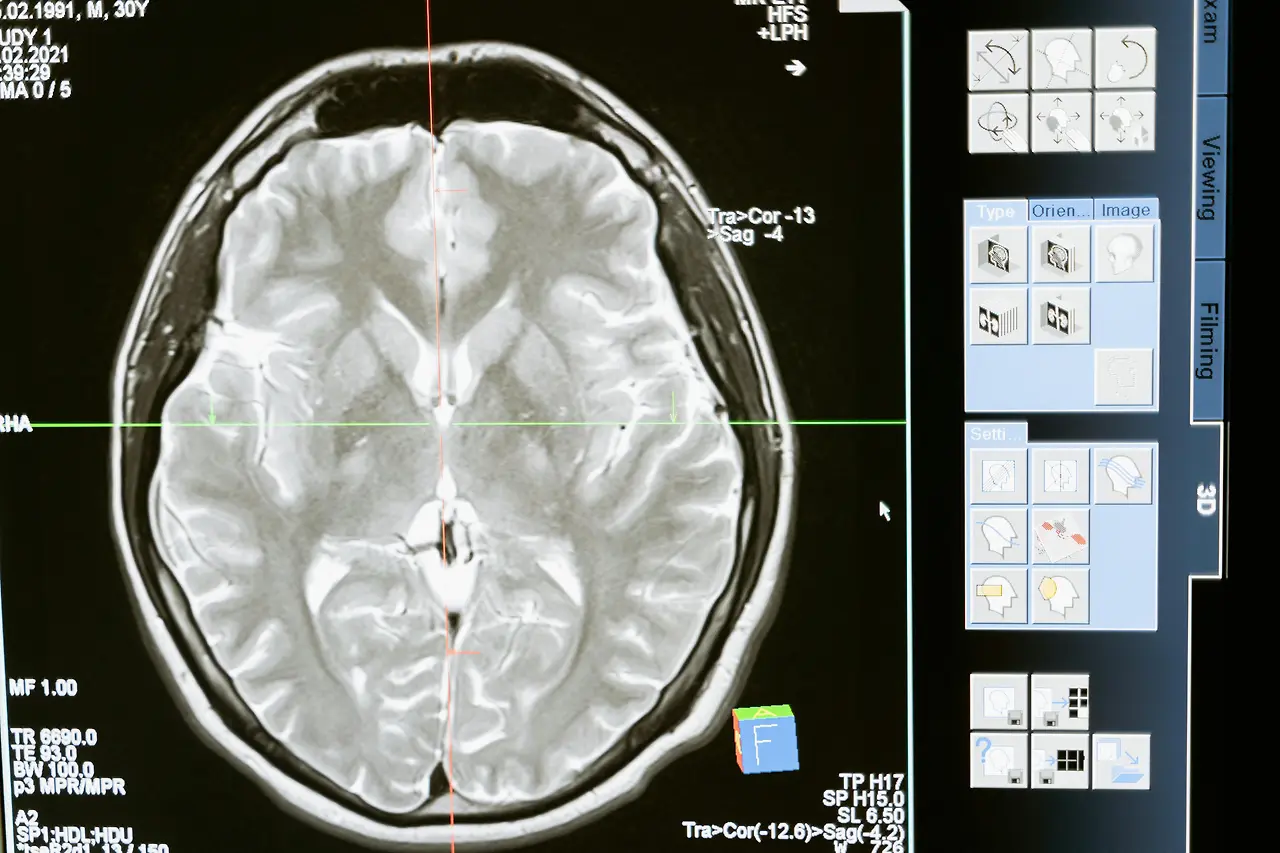

그러나 인간의 뇌는 쾌락과 자극을 조절하는 기능이 있는데 뇌의 전전두엽은 감정 조절과 충동 조절, 계획 및 실행하는 능력과 절제하는 이성적 판단을 하는 모든 인지 기능을 담당하는 기관이다.

전두엽은 어려서부터 20세까지 성장하고 발달한다.

그러나 성장기 뇌의 앞부분에 위치한 전전두엽이 완전히 성장하지 않은 청소년 시기에 인터넷 게임이나 강한 자극에 자주 노출되면 헤마가 정상적으로 성장할 수 없고 당연히 인지 기능을 담당하는 전두엽이 정상적인 발달을 못하는 것이다.